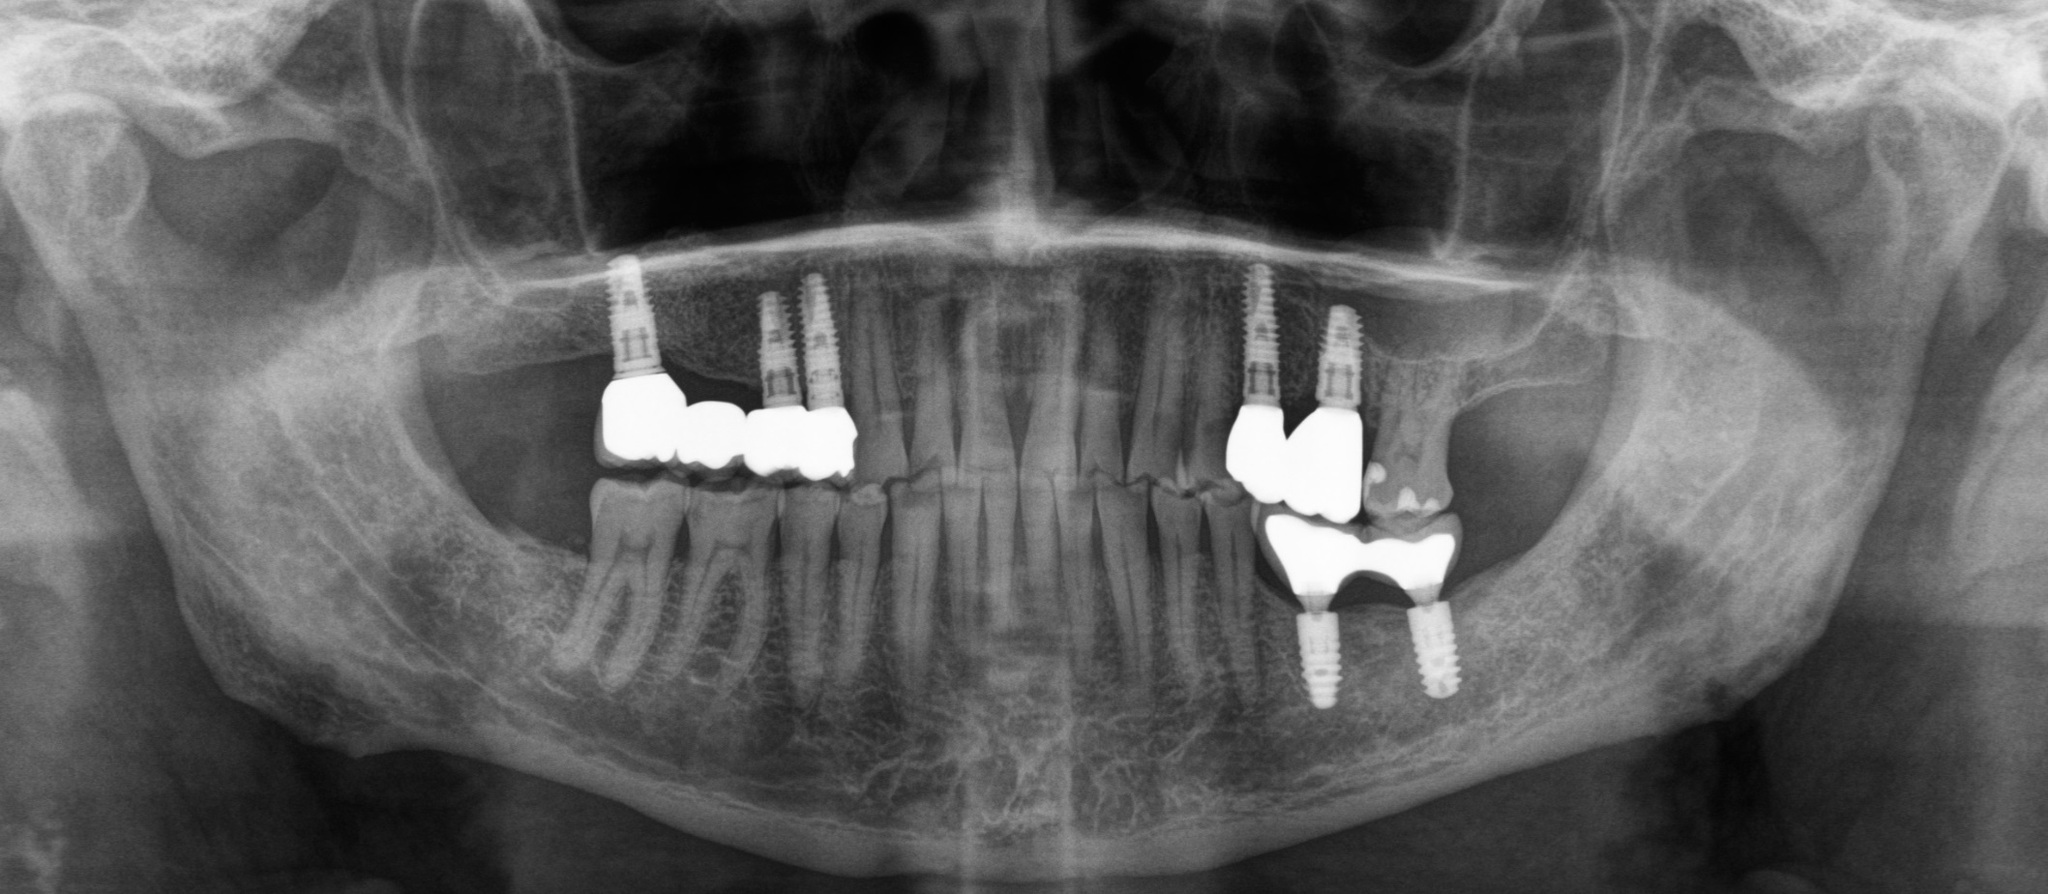

Первым контрольным рентгеновским снимком был этот:

На установленных ранее имплантатах в области 5 и 7 зубов на верхней челюсти справа (на снимке слева) стоял временный мостовидный протез. Пластик, из которого изготовляются временные конструкции не рентгеноконтрастен. Поэтому ничего кроме «белых полосок» в этой области вы не увидите. Средний срок службы подобных конструкций три месяца, но «по семейным обстоятельствам» пациент пользовался ими дольше обычного. Это привело к тому, что мостовидный протез треснул, аки старый трухлявый деревенский мост. В связи с этим, собственно, пациент и явился на прием. Напомню название статьи – «бруксизм». Сложно не заметить отсутствие зубов на противоположной стороне челюстей. Отсюда можно сделать логичный вывод, что основное (если не единственное) пережевывание пищи осуществлялось на стороне, где установлены имплантаты.

На снимке ниже перелом временной коронки:

Было проведено удаление 6 и 8 зуба на нижней челюсти слева (на снимке справа).

После чего пациент был направлен на ботулинотерапию с целью коррекции гипертонуса жевательных мышц. Пропав на три месяца, в июле 2018 он вернулся для установки новых временных коронок на верхней челюсти справа: